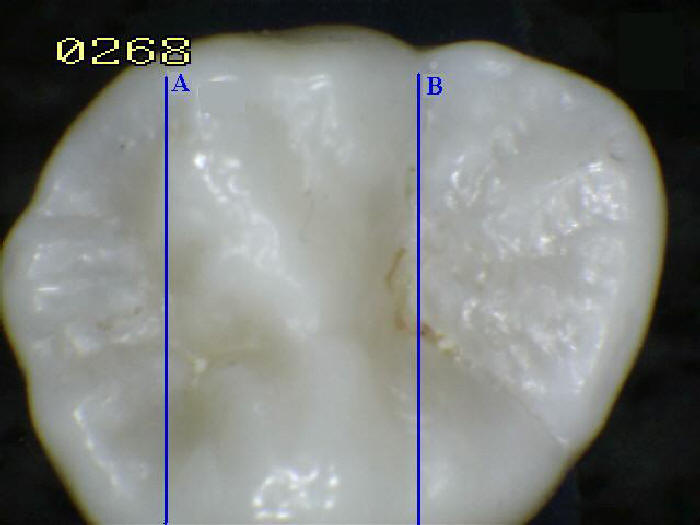

VAINAS DE ESMALTE

[10] La gran cantidad de minerales

en el esmalte explica no solo su resistencia

sino también su fragilidad. [8] La dentina, que

es menos mineralizada y menos frágil, compensa

el esmalte y es necesaria como soporte. [10] A